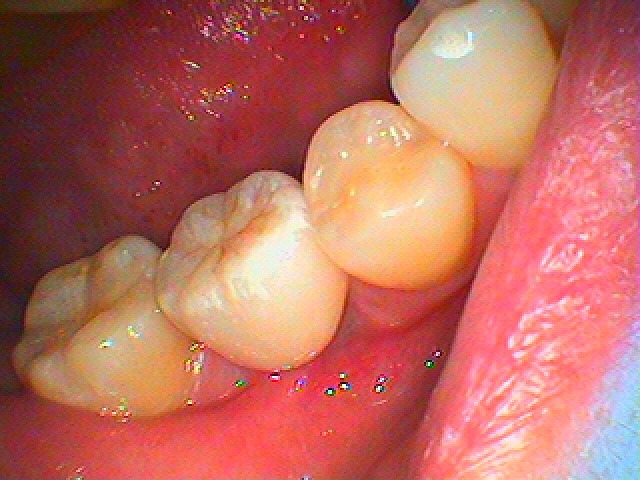

最終補綴が入りました

このように綺麗に仕上がりました